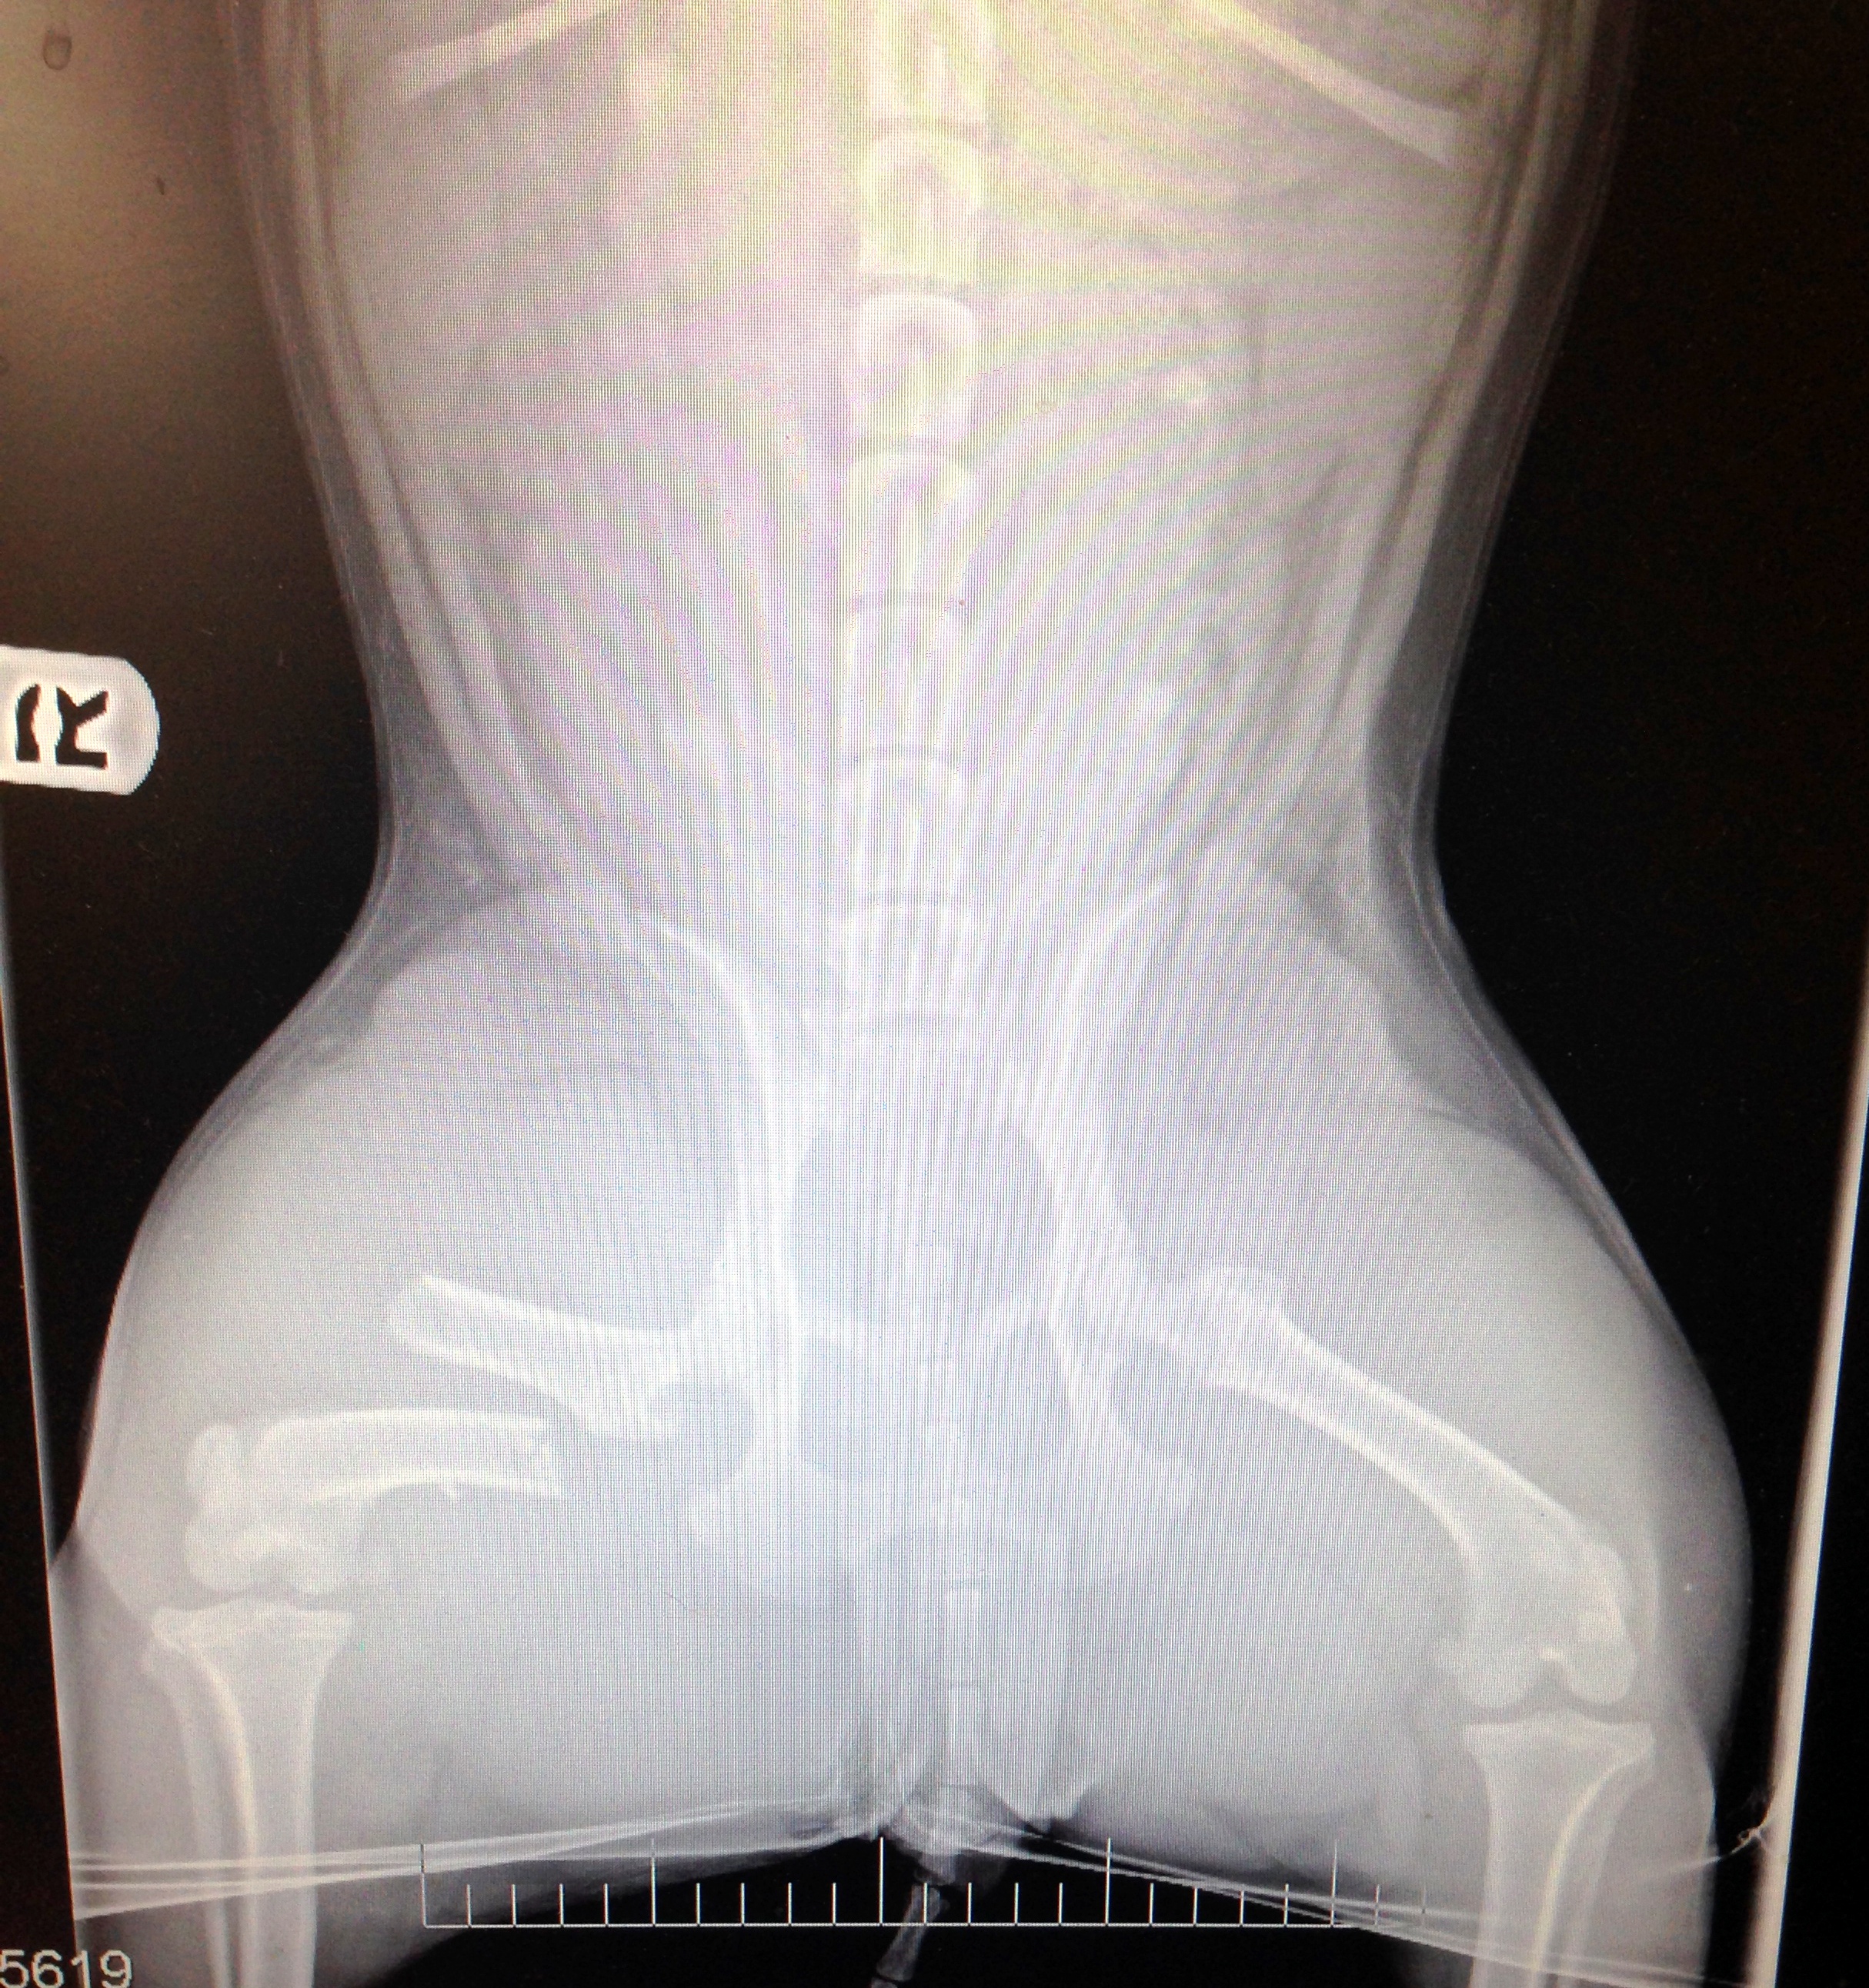

PawUpHoneyXray

***Honey Needs ALL Our Help!!!!!***

Being in the right place at the right time can mean life or death...a relative of one of our volunteers was driving in Torrance. She saw a young dog get hit by a car. She got out of her truck and the injured pup came right up to her. She immediately took her to an ER vet, she was scanned for a chip and her owner was contacted. What should have been a feel good moment turned into a a crushing blow.

The owner didn't care about their dog...they said to euthanize her. The vets office had Animal Control call and they told them the same thing...they didn't care or want her anymore. The vets office gave our good samaritan only a few hours to either pay the medical or they were euthanizing her...

We weren't going to let that happen and now Honey is our vet getting the immediate medical attention she needs. Honey has lacerations on her head, some truama and a badly broken Femur. She will need surgery to repair and stabilize the break. Now we need YOUR help! We couldn't let this young girl die because her family didn't care about her.

Please consider making a 100% Tax Deductible donation towards her medical care. Honey is a doll and deserves all the help we can give her! No donation is too small! THANK YOU!! - See more at: Click here to help Honey